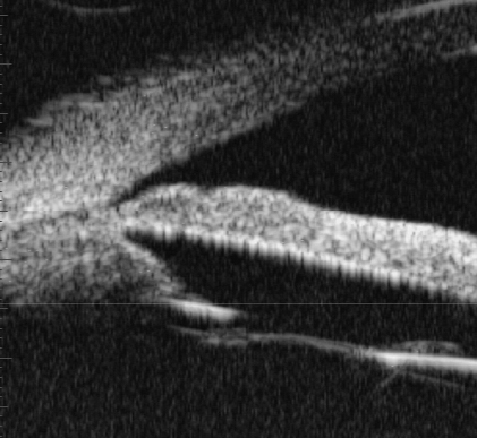

Figure 9 of Yu, Mol Vis 2012; 18:1074-1082.

Figure 9. The group B show the chamber angle are opening at 12 month after operation (in terms of UBM).